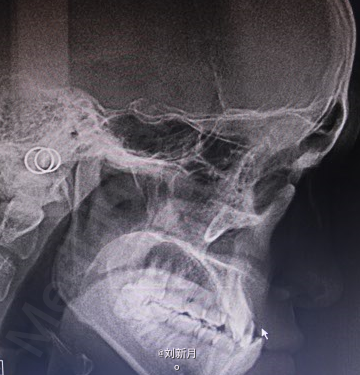

主诉:地包天求矫治 既往史:无矫治史,无牙科治疗史,无外伤史,无过敏史,无口腔不良习惯,无家族遗传史 口腔检查:恒牙列,A7-B7;C7-D8。牙齿排列整齐 尖牙磨牙III类关系,前牙反合 中线对正 面型为凹面型 关节无弹响无压痛

口腔检查 前牙反覆合,反覆盖 拍头颅侧位片,曲面断层片